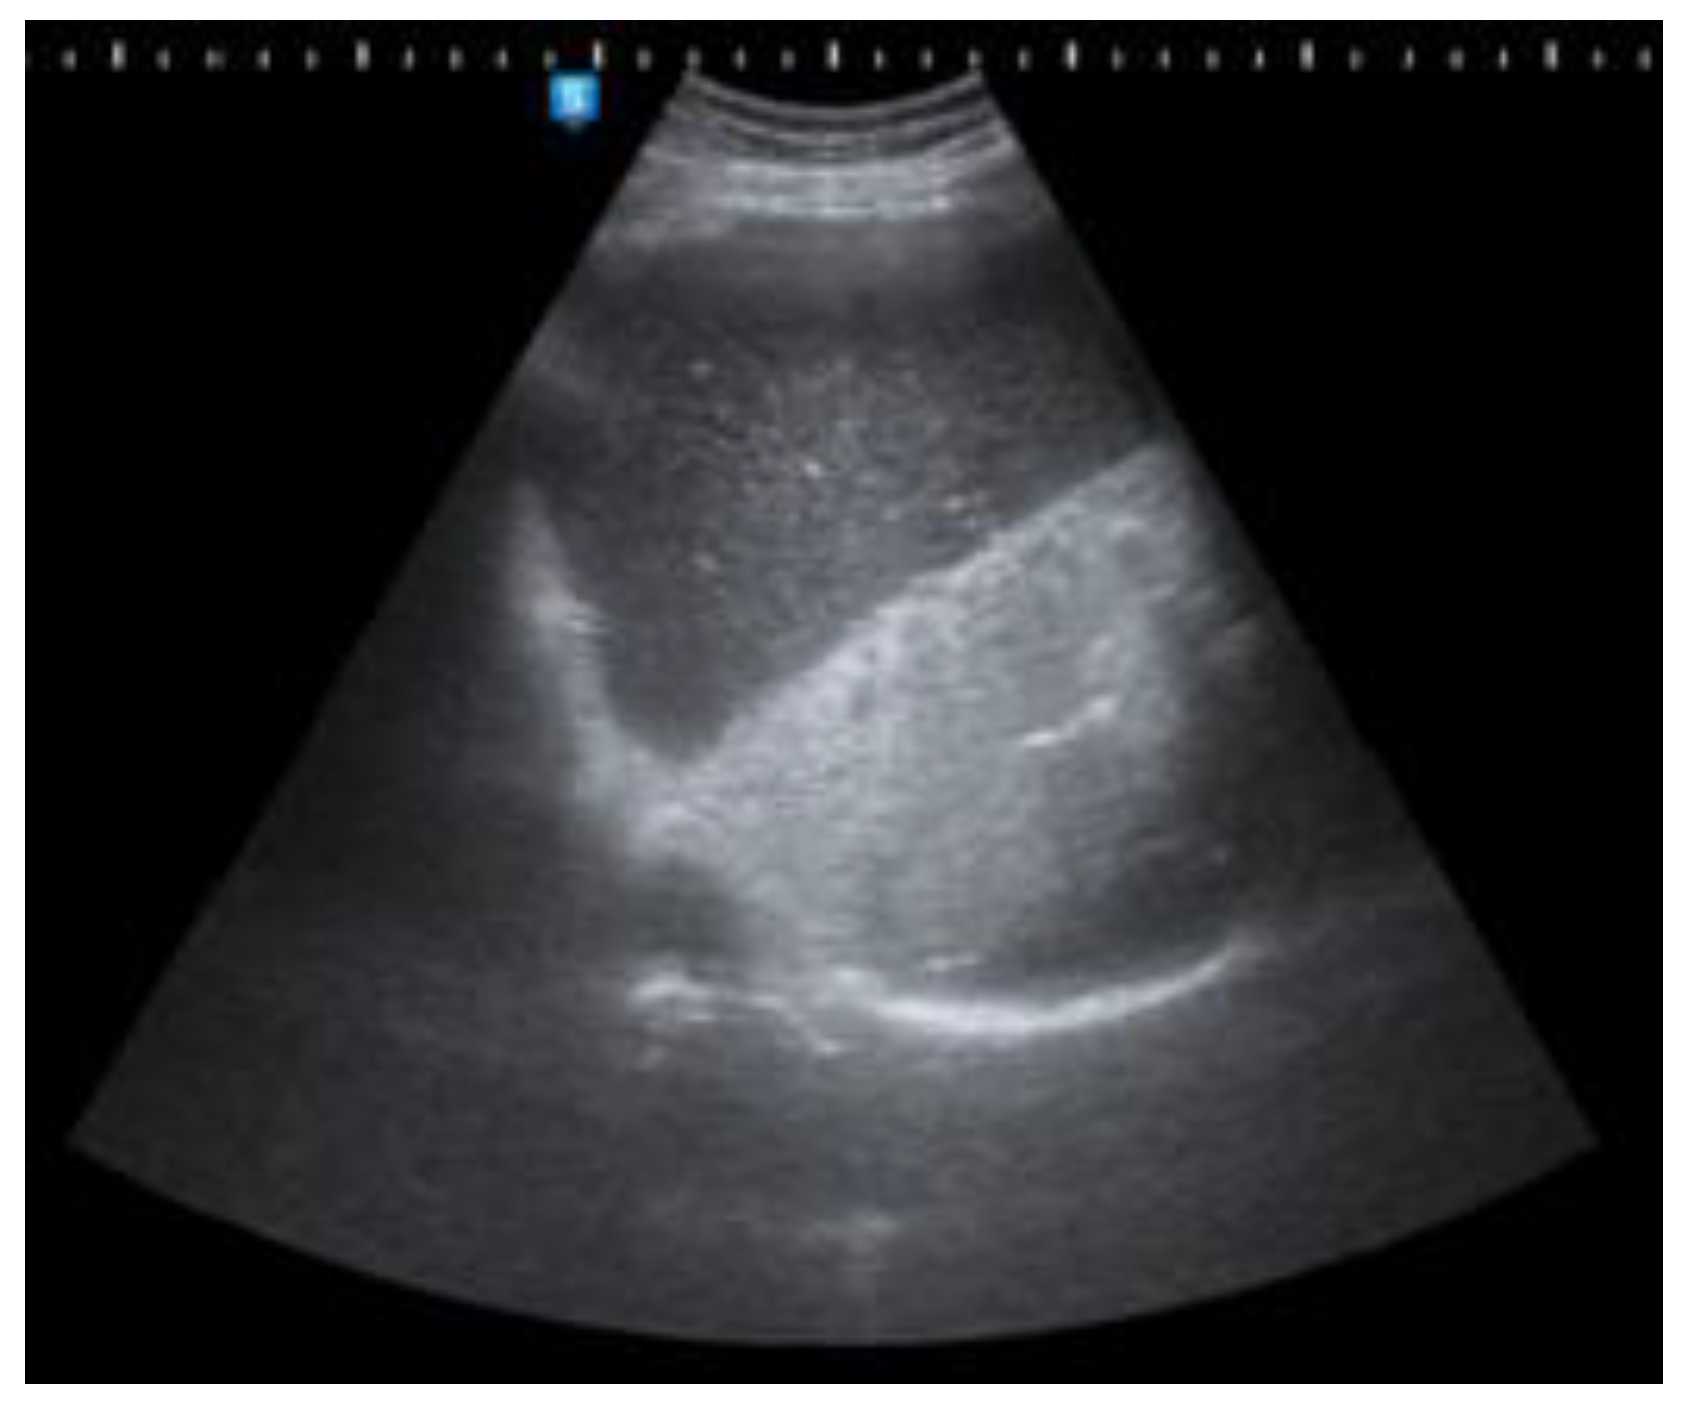

Figure 2, Figure 3 and Figure 4 Abdominal ultrasound (US) also demonstrated an enlarged stomach, a curvilinear focus of increased echogenicity with posterior shadowing in duodenal bulb which corresponds to a gallstone (long arrow) and ultrasound signs of pneumobilia. The leading diagnosis of a new finding of pneumobilia on ultrasonography with elevated white blood cell count is cholangitis. However, poor visualization of gallbladder and distended stomach can not be explained by cholangitis so CT scan has been useful as an imaging modality for diagnosis of cholecystoduodenal fistula. The other causes of pneumobilia are biliodigestive anastomosis or post-ERCP conditions.

Figure 2. Transabdominal ultrasound.

Preprints 107205 g002

Figure 3. Transabdominal ultrasound.

Preprints 107205 g003

Figure 4. Transabdominal ultrasound.

Preprints 107205 g004